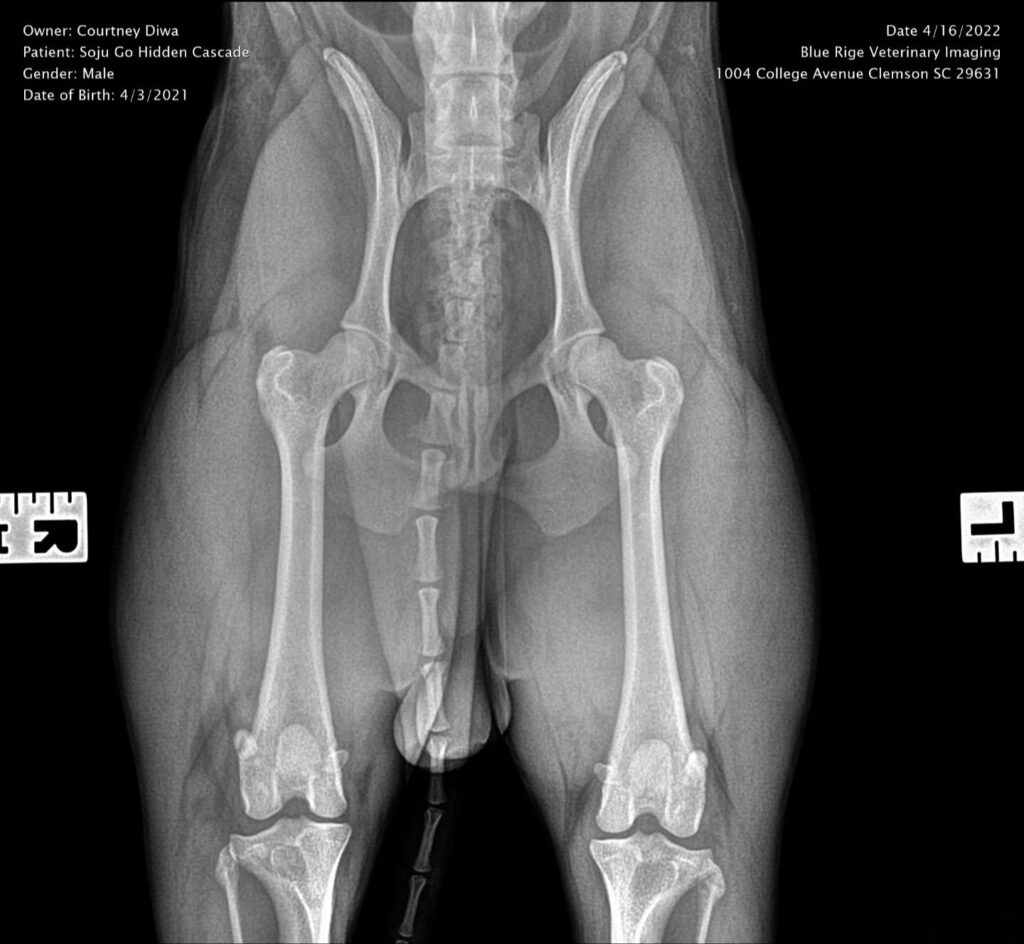

CH Soju go Hidden Cascade TKN

Titles & Health Certificates